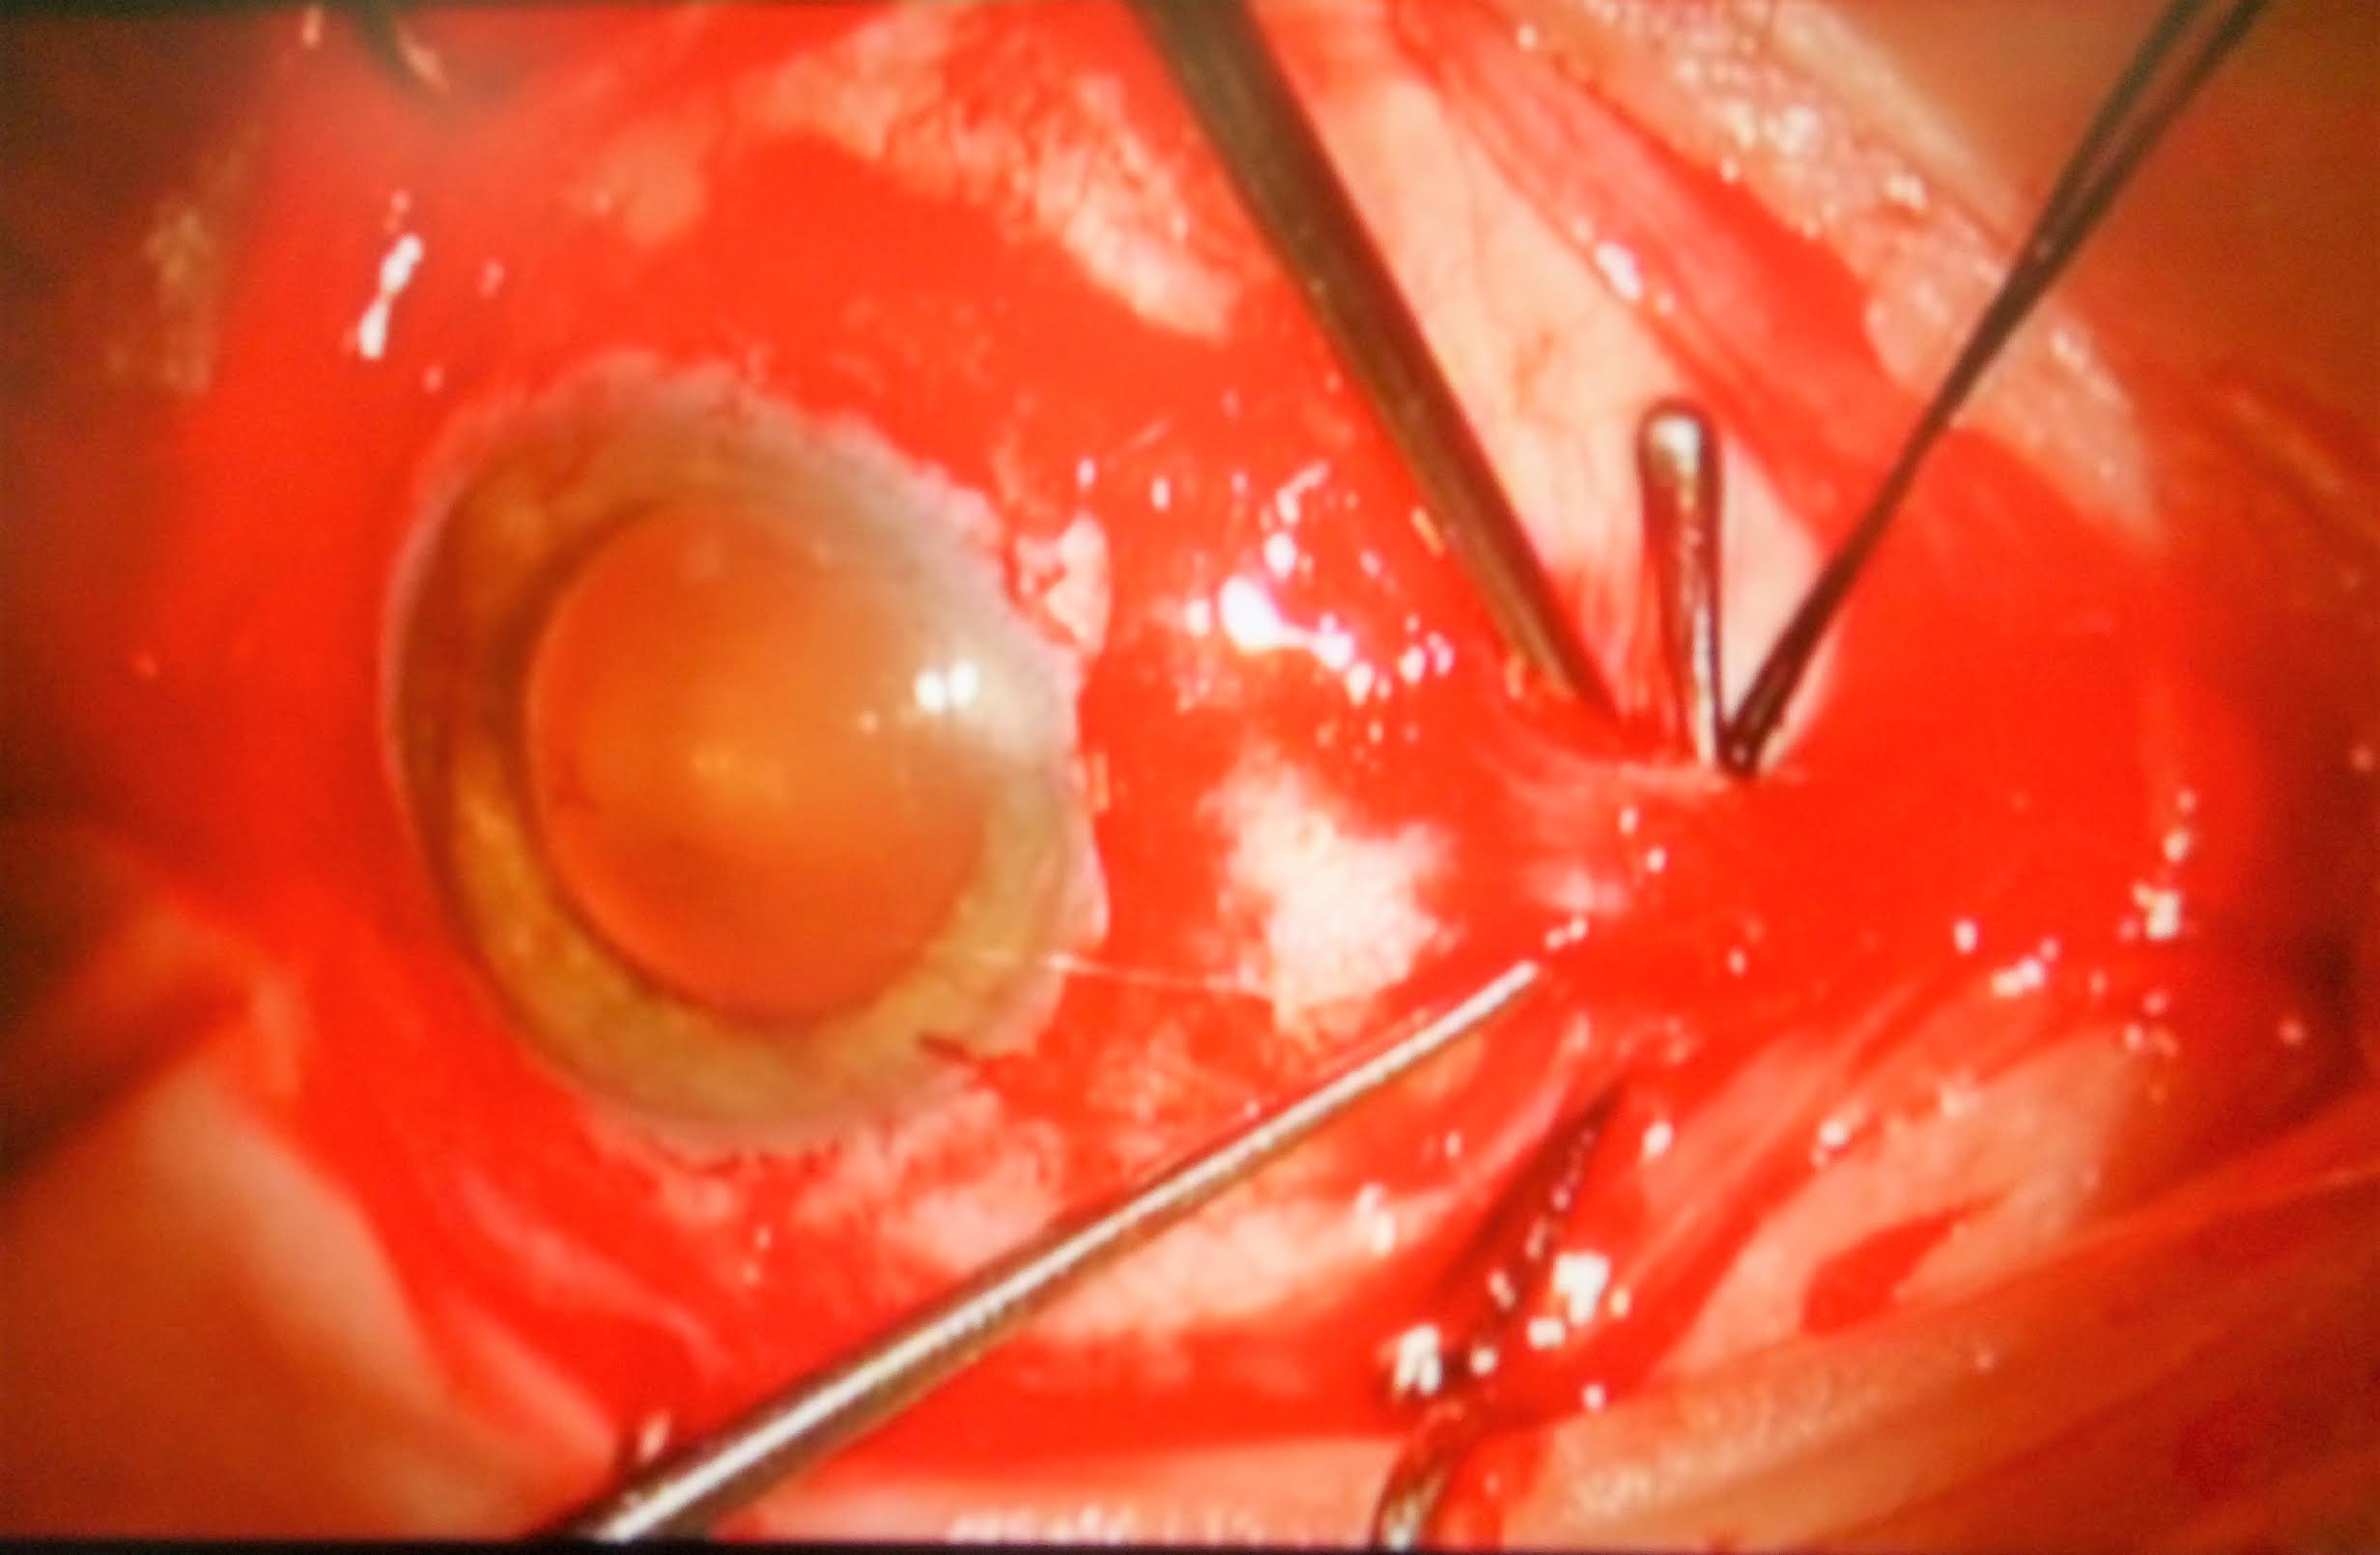

10 Intervento di chirurgia episclerale per distacco di retina

Paziente di 67 anni riferisce forte calo visivo nell'occhio destro da alcuni giorni, l'obiettività oculistica era la seguente:

Visus 2/50 non migliorabili con lenti

tono 11 mmhg

biomicroscopia nella norma

fundus: distacco di retina macula off (coinvolgente anche la macula) da ore 3 a ore 9 circa con duplice rottura retinica ore 6 circa

Effettuata chirurgia episclerale (cerchiaggio)

1) Peritomia congiuntivale su 360° isolamento dei muscoli retti e posizionamento dei fili di trazione) foto 1

2) Posizionamento di fibra ottica per esplorazione del fundus con sistema biom foto  2

3) Localizzazione delle rotture retiniche e criotrattamento foto 3

4) Cerchiaggio con spugna in silicone foto 4

5) Puntura evacuativa e drenaggio del fluido sottoretinici foto  5

6) Controllo indentazione delle rotture foto 6

7) Sutura congiuntivale foto 7

Il decorso post operatorio è stato regolare